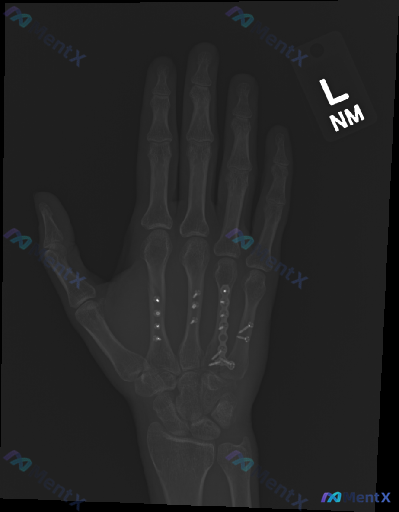

这是一个左手掌骨术后复查的影像学病例讨论。X光片显示第3、4、5掌骨存在金属内固定物,骨痂生长尚可;但围绕内固定系统的稳定性、是否存在隐匿风险,有多个观察与判断方向值得梳理。

整理了一份左手第3掌骨术后的侧位X光片资料,先看一下影像描述: - 第3掌骨掌侧可见钢板及多枚螺钉内固定 - 骨折线已不明显,解剖序列基本正常 - 未见明显急性脱位、异常肿胀或异物 - 报告最终考虑为“术后内固定状态” 但仔细想一下,这张侧位片真的能完全排除“不正常”吗? 大家觉得这份影像里,最容易...